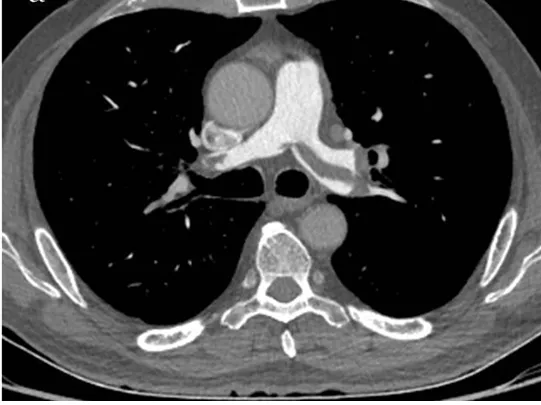

58세 여성이 갑작스러운 호흡곤란과 가슴 통증을 호소하며 내원했다. 5주 전에 왼쪽 슬개골 골절로 인해 수술을 받았다. 혈압은 130/80 mmHg, 맥박은 102회/분, 호흡수는 24회/분, 체온은 37.1도로 측정되었다. 흉부 CT 촬영 결과를 바탕으로 가장 적절한 치료 방법은 무엇인가?

Imp: Pulmonary thromboembolism

갑작스러운 호흡곤란과 흉통 및 빈맥, 5주전 슬개골 골절 수술 히스토리는 폐색전증을 강하게 시사하는 소견이다. CT상에도 폐동맥의 저음영 병변이 보이므로 diagnostic하기 때문에 추가 검사 없이 치료로 넘어간다.

• 바이탈이 안정되어 있으므로 이차 예방을 위한 항응고치료 단독요법을 시작한다. 헤파린 브릿징 없이 와파린을 사용할 경우 역설적으로 thrombotic effect가 나타날 수 있으므로, 처음 시작은 NOAC이나 heparin으로 해야 한다.